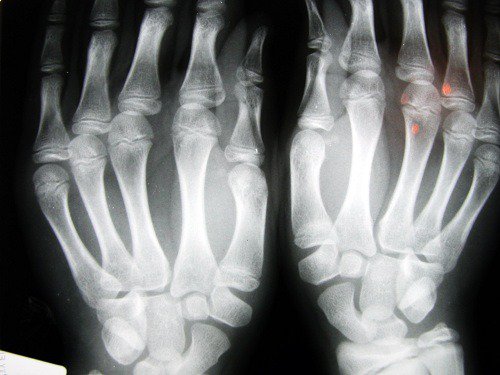

2. 変形性膝関節症のリスク

イギリスにあるノッティンガム大学の研究によると、人差し指が短い人は変形性膝関節症を発症するリスクが高いとされています。

これはエストロゲンの不足や運動不足に関連しており、主に女性にその影響が見られます。

3. 前立腺ガン

イギリスのウォーウィック大学の発表では、人差し指が薬指よりも長い男性は、将来、前立腺ガンになるリスクが高いことが発見されました。